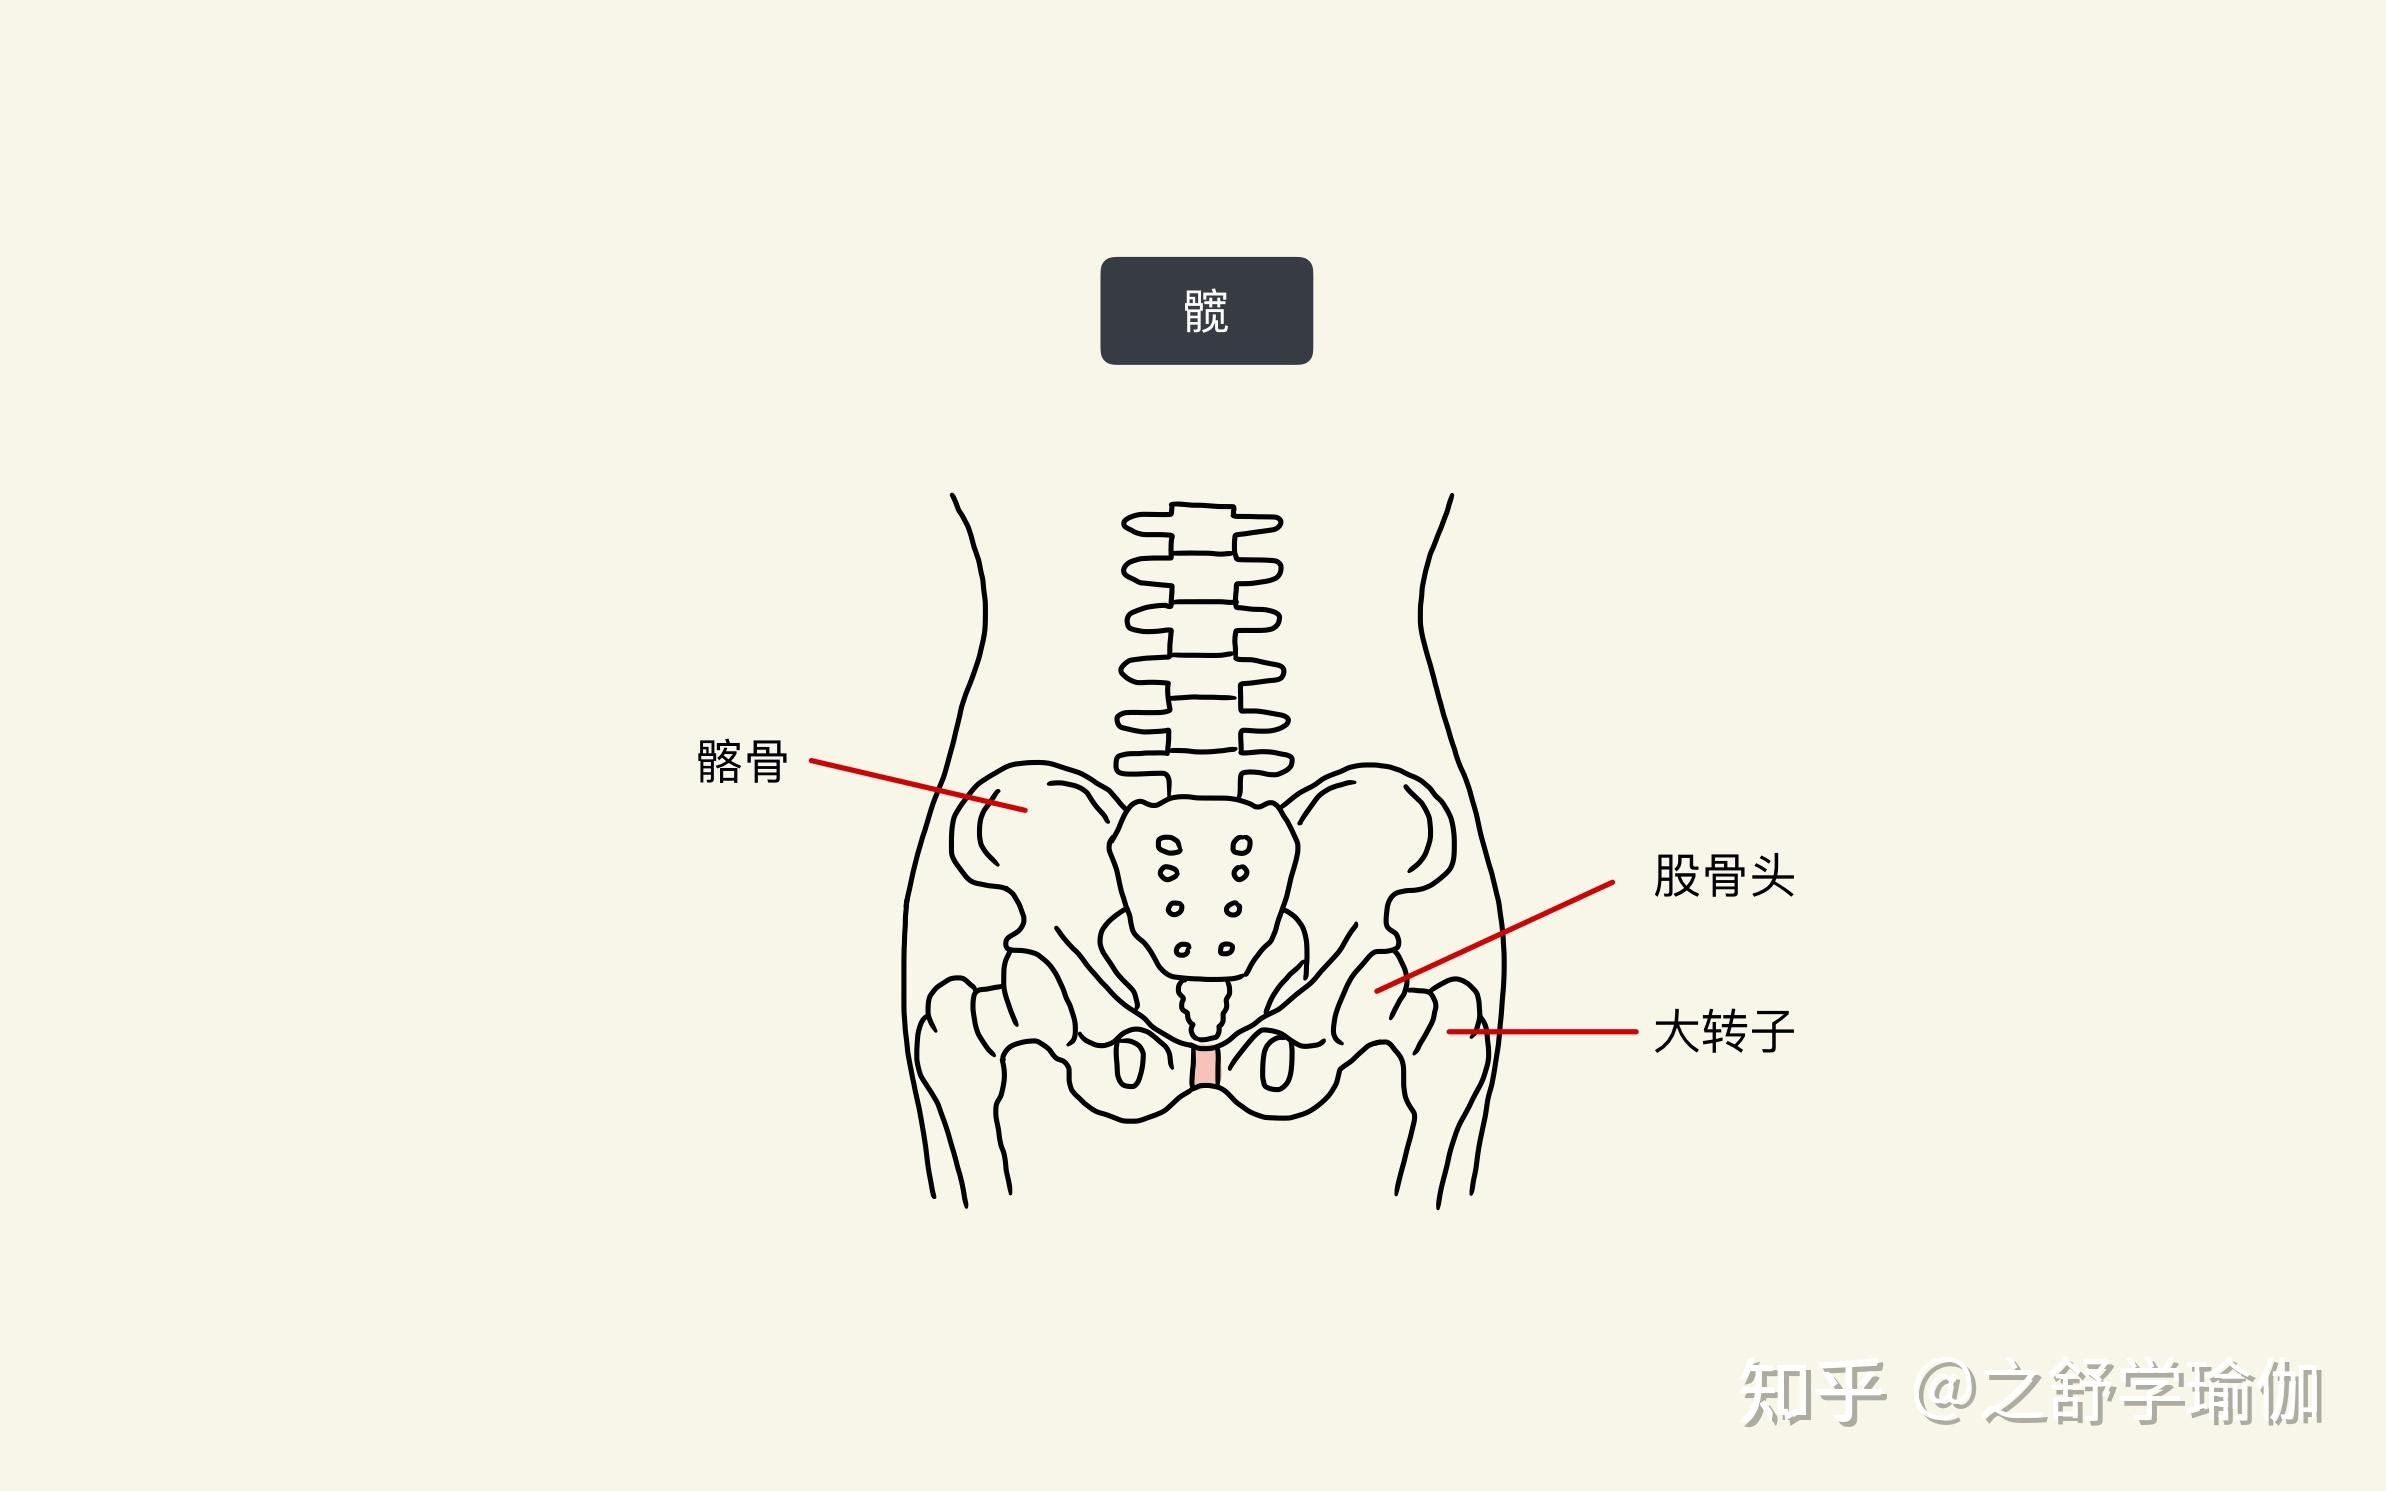

胯骨图片

股骨头是人体关节的一个组成部分,呈圆形,也就是我们通常所说的"胯骨

骨骼日记之髋骨 简介: 髋骨为不规则骨,由髂骨,耻

到青春期结束时,三个区域将融合在一起,到25岁时